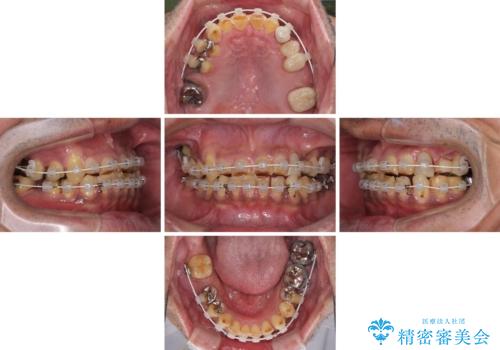

- すり減った前歯や奥歯の銀歯を気にして来院された患者様です。

骨格的な反対咬合により上顎前歯の先端が顕著にすり減っている状態でした。

奥歯の欠損が散見されており、銀歯の装着されている歯も多いため、ワイヤー矯正にて歯列を調整し、その後オールセラミッククラウンにて補綴治療を行うこととしました。

反対咬合改善には奥歯の咬み合わせをしっかりと改善させることが必要となりますが、奥歯に欠損が多いため、矯正治療が難航することが予想されます。